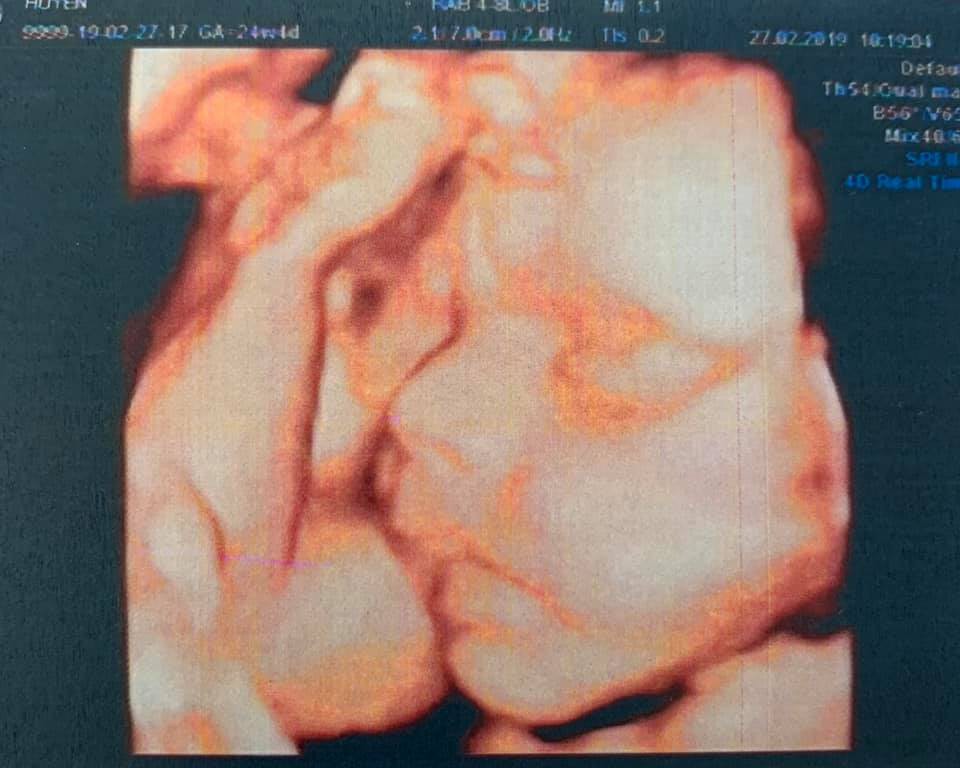

Trên Facebook cá nhân, Hải Băng vừa chia sẻ bức ảnh chụp siêu âm bé thứ ba kèm dòng trạng thái: “Trộm vía lắm em khỏe mẹ cũng ổn định. Bầu 3 đứa đi siêu âm đứa nào mũi cũng cao, mà đẻ ra thì đứa nào cũng tẹt, không giống hai ông bà già nhà nó gì hết“. Ngoài ra, ở phần bình luận bài đăng, Hải Băng còn tiết lộ với một người bạn rằng cô sẽ sinh bé vào cuối tháng 5 tới.

Hải Băng khoe ảnh siêu âm của con, phát hiện có nhiều nét giống bố.